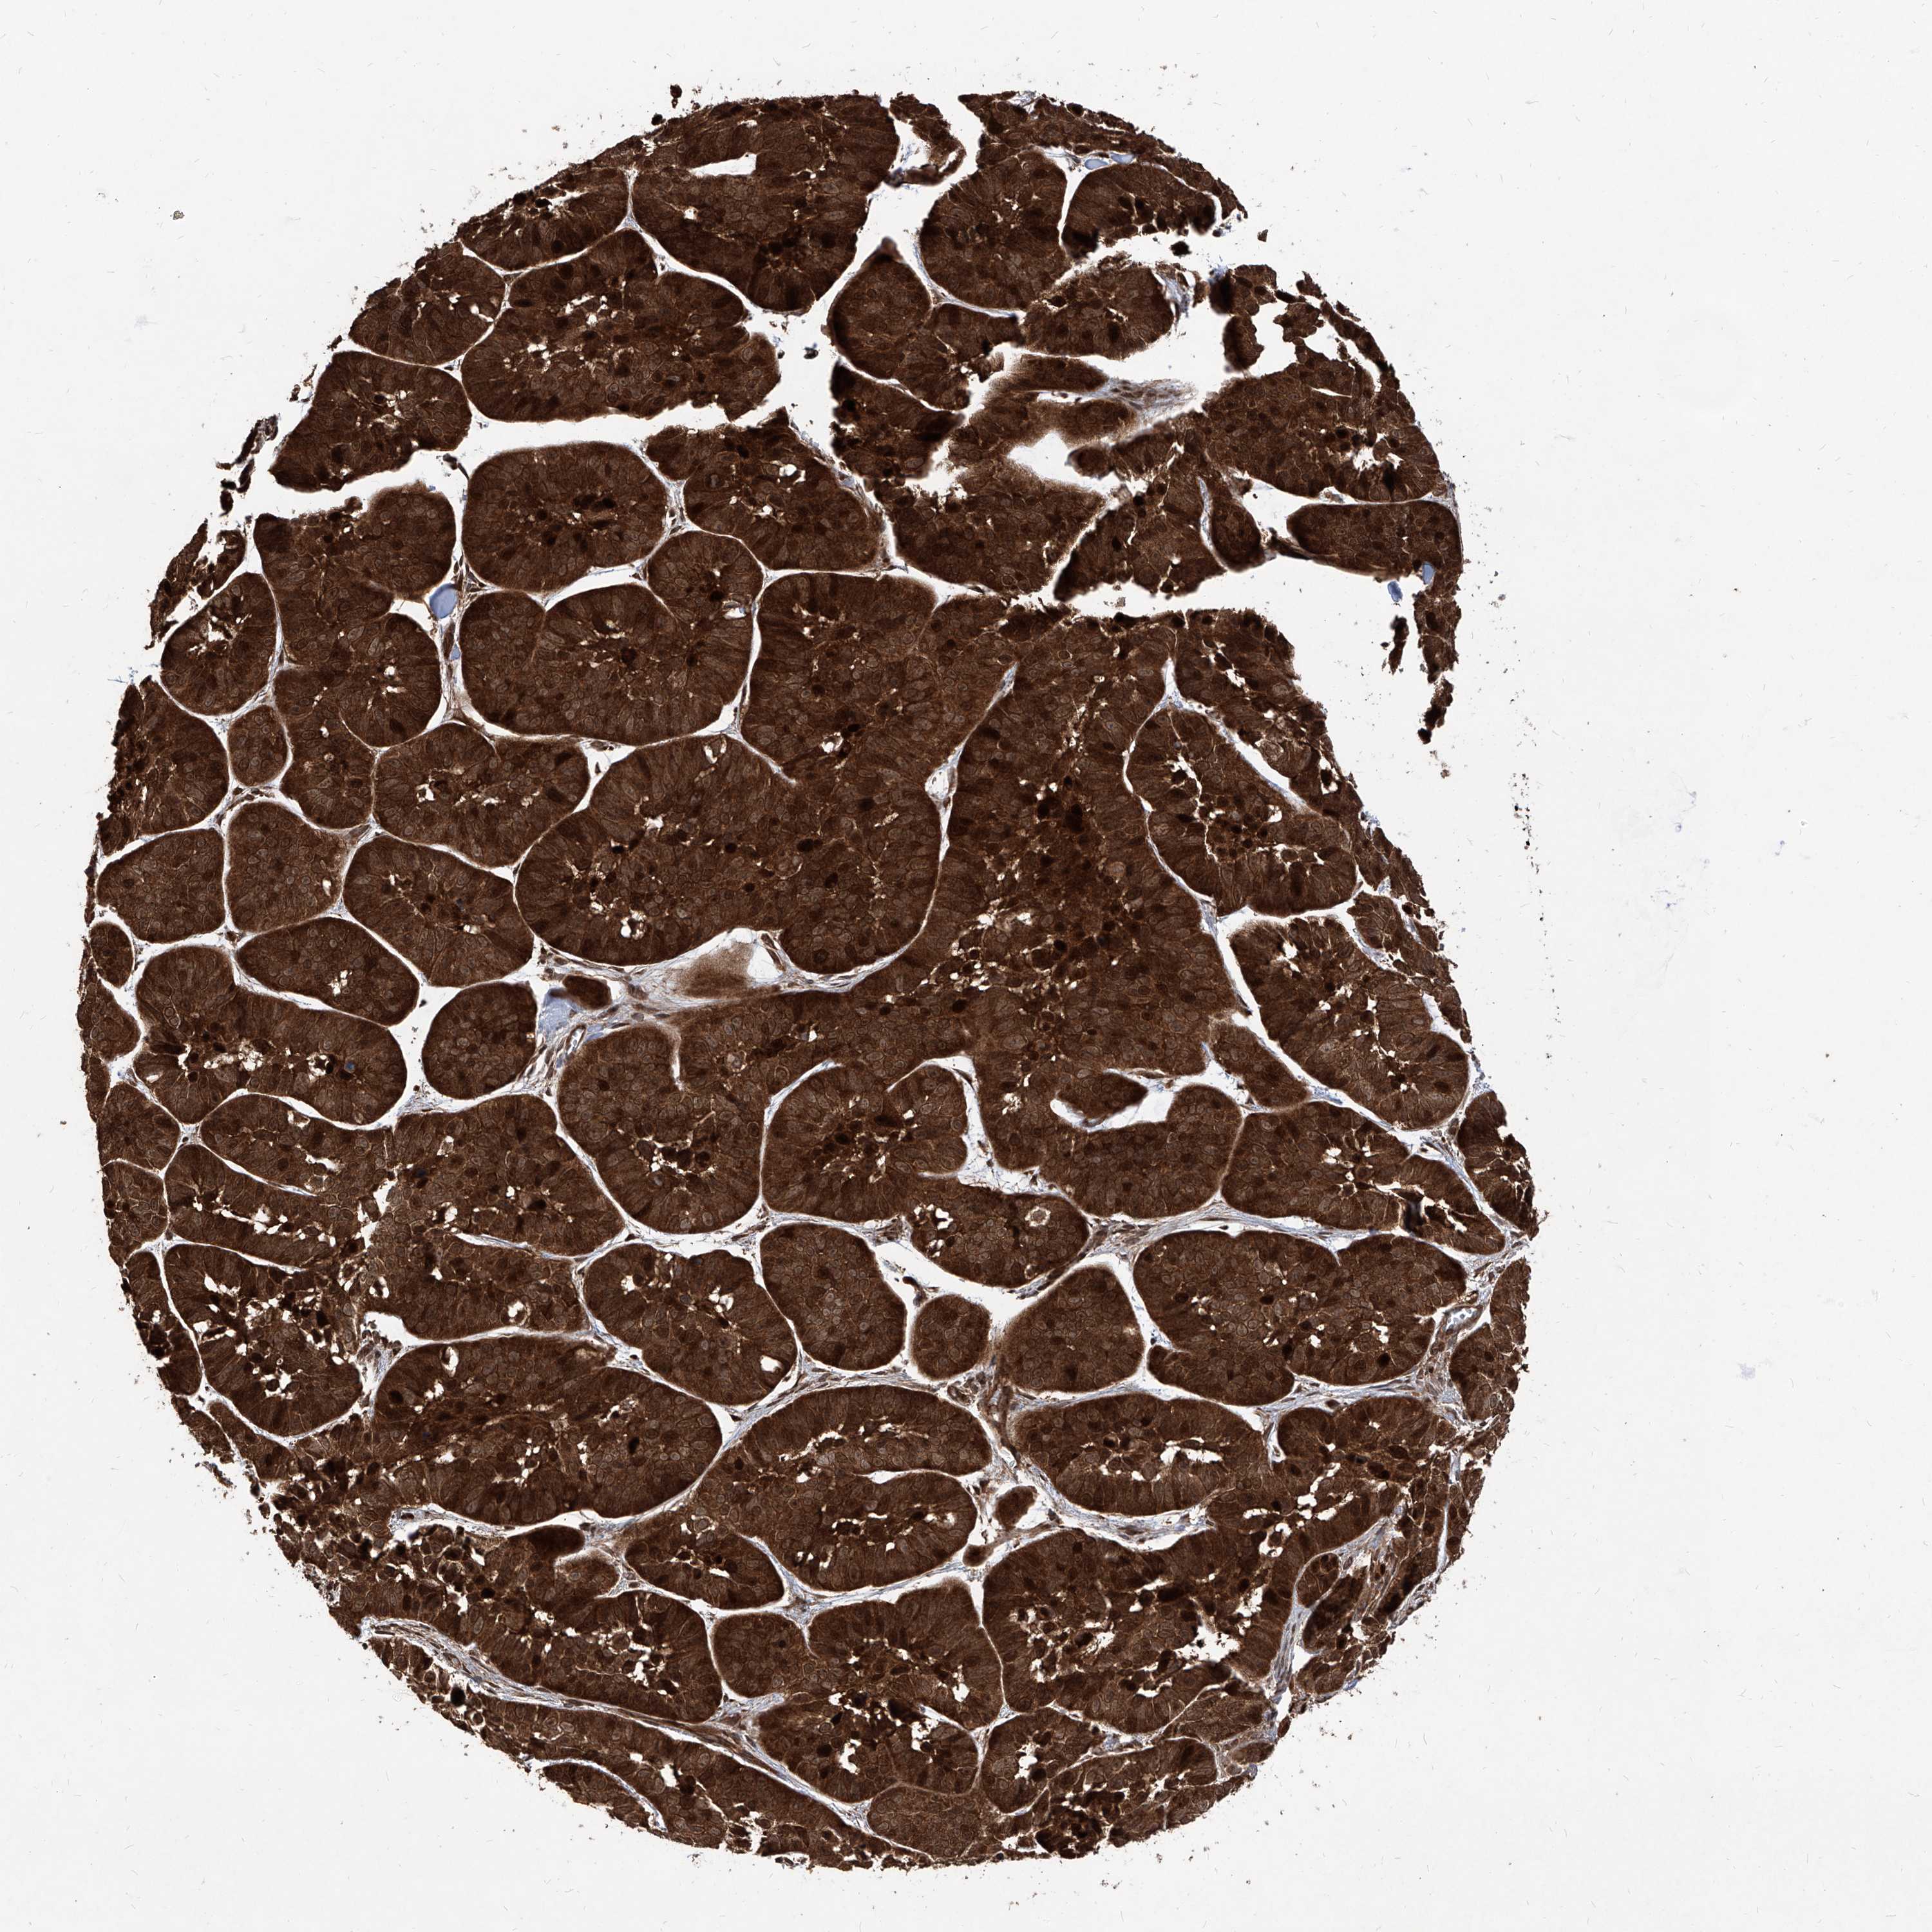

Basal cell and squamous cell cancer

SKIN CANCER - Protein expressioni

A mouse-over function shows sample information and annotation data. Click on an image to view it in a full screen mode. Samples can be filtered based on level of antibody staining by selecting one or several of the following categories: high, medium, low and not detected. The assay and annotation is described here.

Each image is clickable and will lead to virtual microscopy that enables deeper exploration of all samples and also displays staining intensity scores, fraction scores and subcellular localization as well as patient and tissue information for each sample.

Antibody HPA031572

Antibody HPA031573

Basal cell carcinoma

Squamous cell carcinoma, NOS

Squamous cell carcinoma, metastatic, NOS